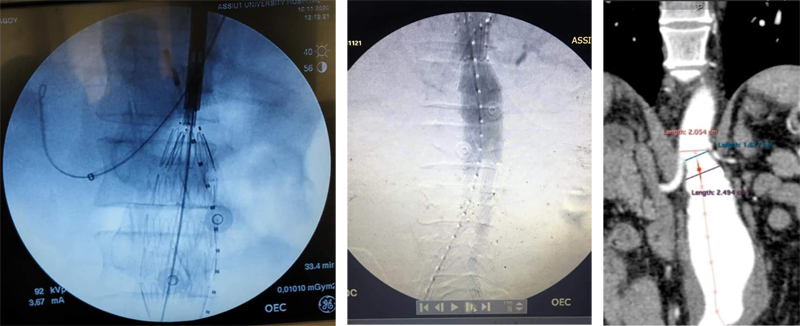

أعلن قسم جراحة الأوعية الدموية بكلية الطب جامعة أسيوط نجاح فريق طبى مكون من الاستاذ الدكتور/ أيمن حسب الله والأستاذ الدكتور/ أحمد حسن بكر والأستاذ الدكتور/ هيثم علي حسن والأستاذ الدكتور/ محمود إسماعيل فى علاج أحد الحالات المعقدة من تمدد الشريان الأورطى البطني المجاور لشرايين الكلى. وتم علاج المريض بأحدث الطرق على مستوى العالم chimney EVAR عن طريق القسطرة التداخلية بدون جراحة والتي تشمل تركيب دعامة مغطاة للتمدد الأورطى البطني وأيضاً تركيب دعامة مغطاة لشريان الكلى المجاور للتمدد الانيورزمي وأوضح الاستاذ الدكتور/ مصطفى سعد - رئيس القسم أن خطورة هذه الحالة تأتي في وجود التمدد الشرياني الأورطي البطني بجوار شرايين الكلى مما يعرض المريض للفشل الكلوي بالاضافة إلى مشاكل التمدد الأنيورزمي نفسه وقد تم علاج المريض بأحدث الطرق العلاجية والمتبعة بأفضل المراكز على مستوى العالم فى علاج مثل هذه الحالات |